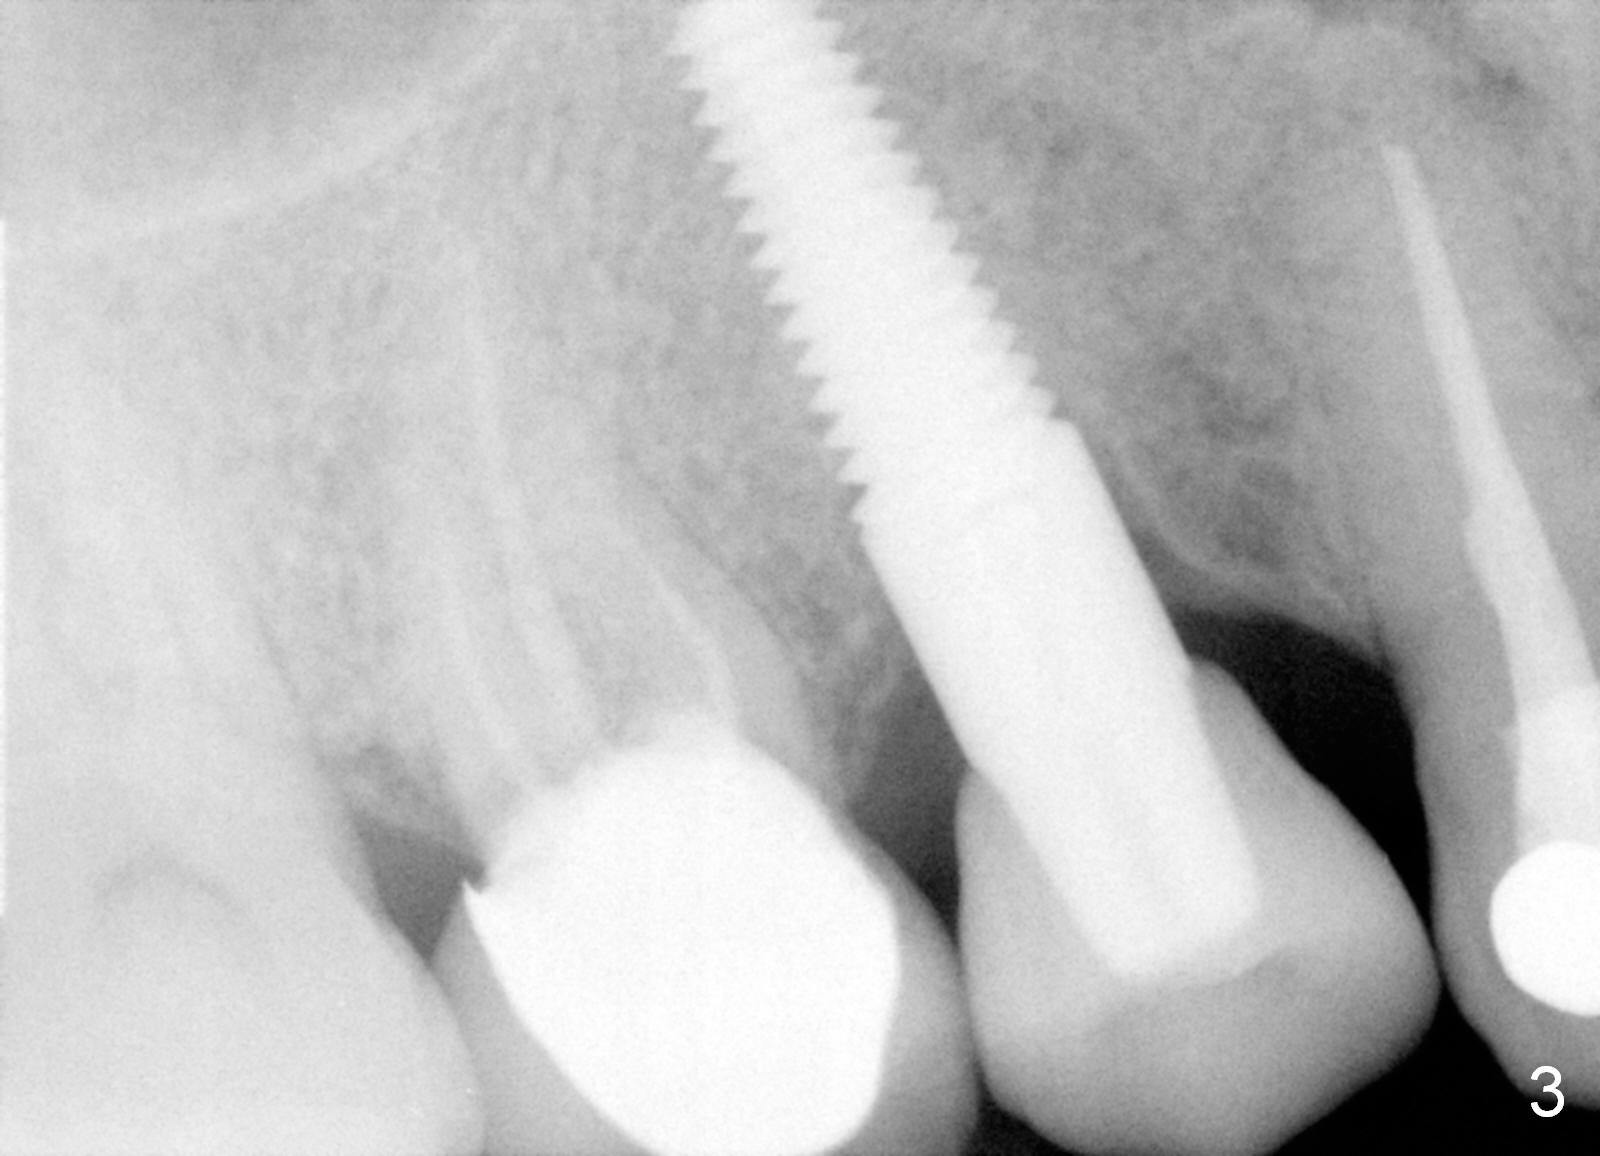

A 47-year-old man has multiple restoration. The crown of the tooth #3 has been recemented several times in the last 3 years (Fig.1). Before placement of an immediate implant at #3 (Fig.2), the root of the adjacent tooth is diagnosed to have crack and replaced by an immediate implant (Fig.3).

The last time the tooth #3 crown was recemented, there was caries in the remaining root stump. The tooth is deemed non-salvageable. The roots will be sectioned prior to extraction. There is no sign of periodontal disease. The bone is expected to be dense. It should be easier to use reamers for osteotomy than expanders or osteotomes. A relatively smaller implant should be able to achieve primary stability in the septum (Fig.4, as compared to Fig.2). The deeper portion of the sockets will be filled with collagen plug, while bone graft is used to cover exposed implant threads. If the 17 mm long implant has questionable stability, longer one will be placed (Fig.5). A 5x5 mm abutment will be most likely used for the shorter implant, whereas a shorter abutment for the longer implant.